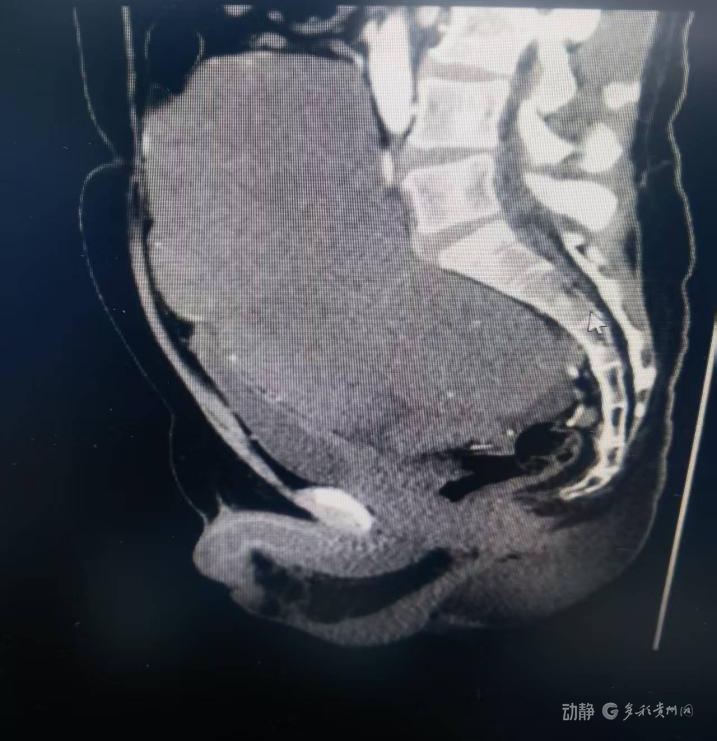

近日,中山一院贵州医院(贵医附院贵安院区)多学科团队成功为一名患者实施高难度盆腔巨大肿瘤切除术,完整摘除重达约13公斤、直径达25厘米的肿瘤,患者术后恢复良好。

据了解,该患者入院时盆腔肿瘤已导致下腹部明显隆起,伴随持续性腹痛、尿频尿急等症状,严重影响日常生活。经全面检查,发现肿瘤与髂血管、输尿管等重要结构紧密粘连,手术难度大、风险高。

手术过程中,医疗团队在麻醉科密切配合下,逐层切开腹部,精准分离与肿瘤粘连的组织,避开重要血管和神经。由于肿瘤血供丰富,且侵犯膀胱壁及直肠前壁狄氏筋膜,操作空间极为有限。历经7小时,团队最终将肿瘤完整切除,并完成止血和切口关闭。